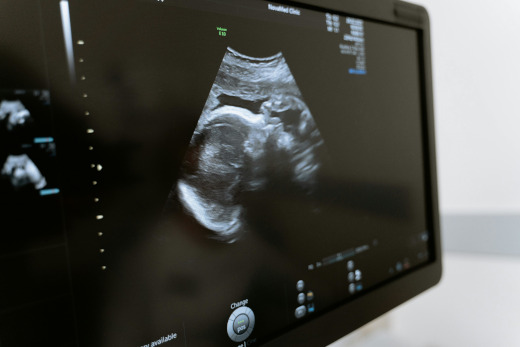

• échographie générale et spécialisée

Radiologie

Échographie générale et spécialisée

Examen indolore pour visualiser les organes en temps réel.